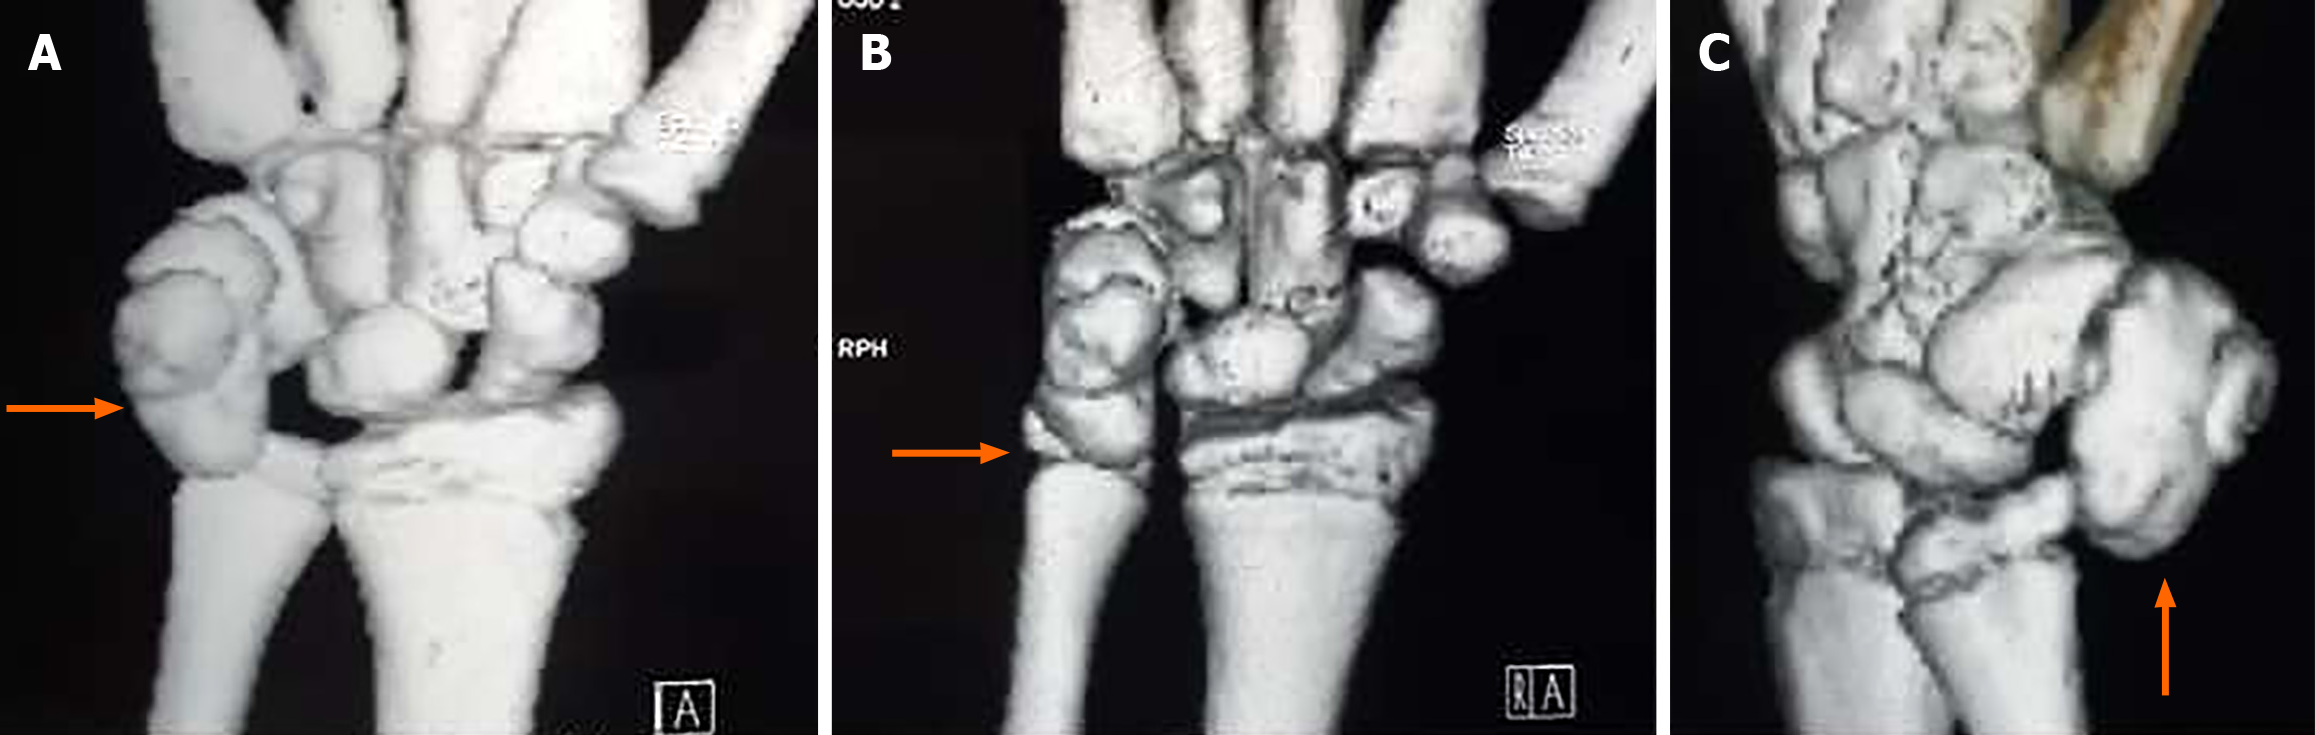

Figure 2 Computed tomography scan demonstrated a well-circumscribed lesion and a small bump ventrally suggestive of pisiform (pisiform with dorsal osteochondroma) with no stalk and no periosteal reaction (3D computed tomography marked).

A-C: Various views of the wrist (anteroposterior and oblique) and the orange arrow pointing the lesion.